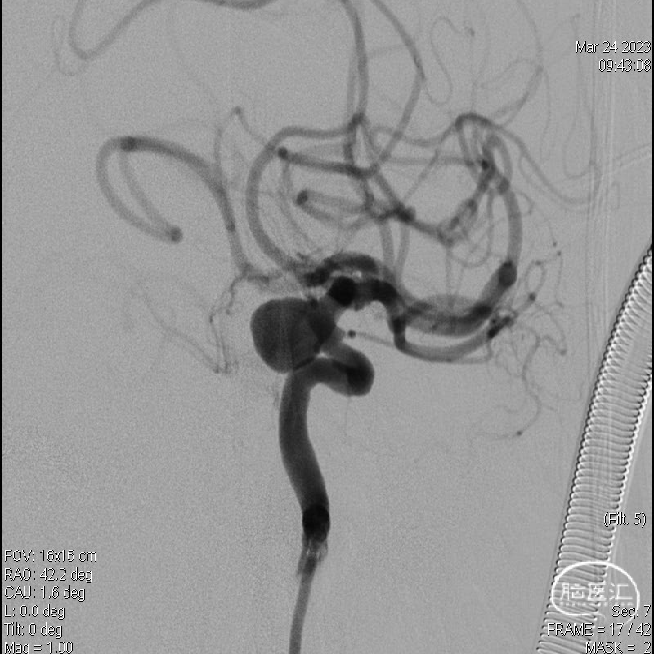

DSA提示左侧颈内动脉C6段大型动脉瘤,囊状,宽颈,选取释放支架(头端)角度及填圈角度。

测量载瘤动脉远端直径3.2±0.3mm,近端直径4.6±0.3mm,预计覆盖长度25mm。

术后工作位造影及蒙片提示支架覆盖动脉瘤颈,位置及贴壁良好,载瘤动脉通畅,动脉瘤即刻基本不显影。

术后蒙片显示Surpass Evolve近乎全程显影,贴壁良好。